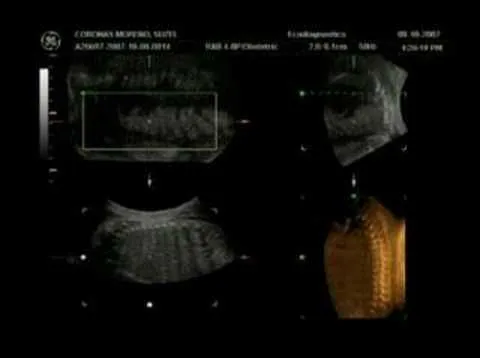

All comments on ultrasonido 19 semanas de embarazo - YouTube

Gabriel Josep Combellas Fabio: Ultrasonido 3D/4D